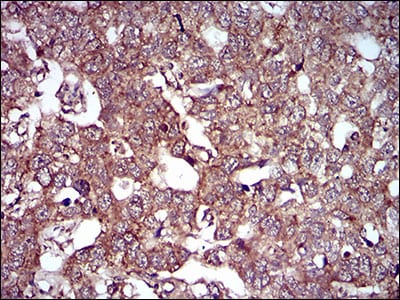

Immunohistochemical analysis of paraffin-embedded human endometrial cancer tissues using ND6 mouse mAb with DAB staining

Immunohistochemical analysis of paraffin-embedded human esophageal cancer tissues using ND6 mouse mAb with DAB stainin